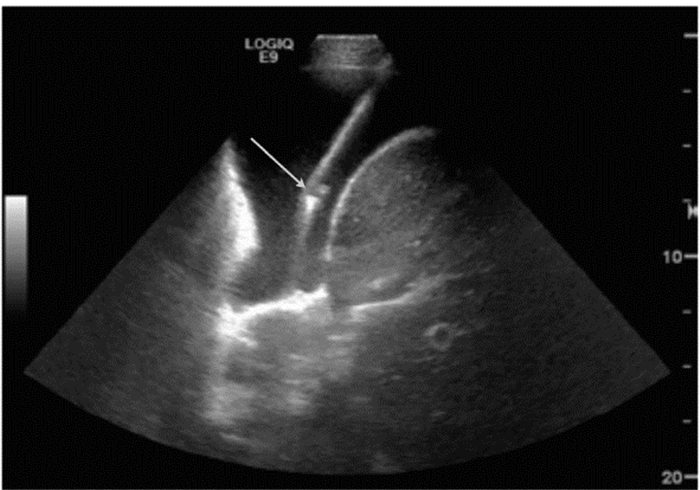

(3)超声引导下心包穿刺术(ultrasound for pericardiocentesis) 心脏压塞是临床常见的危重症之一,多继发外伤或心脏术后、急性心包炎症、恶性肿瘤等基础疾病,需积极的穿刺引流。精准的床旁超声定位下穿刺,对急诊引流心包积液,起着必不可少的作用[50, 51]。临床上床旁心超选择穿刺路径多为剑突下或心尖区途径(图 43)。剑突下途径是在剑突下与左肋弓下缘之间,朝向左肩方向,与皮肤呈15°~30°角将穿刺针刺入心包腔内。心尖区穿刺位点是在左乳头外侧肋间隙,心尖搏动最明显处。具体路径须根据操作者的习惯、手法和心包积液的分布来综合考虑。床旁超声与胸部CT等其他影像学检查相互印证,对于穿刺困难者合理选择体位和穿刺路径尤为重要。

|

| 图 43 床旁心超定位剑突下、心尖部位穿刺示意图 |